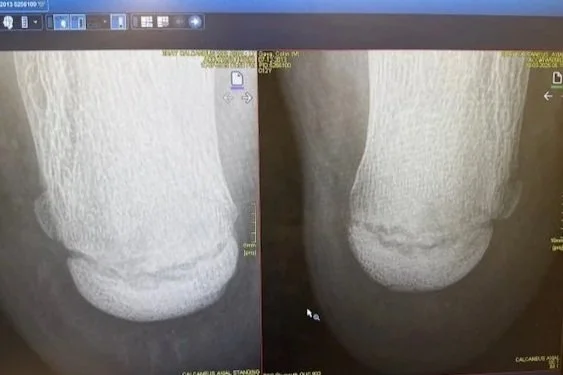

My son Collin started experiencing right foot pain after soccer practice on a Tuesday night. We thought it would be resolved by the morning. The pain worsened to the point that standing on the right foot was intolerable by Friday morning. Orthopedic urgent care revealed that the X-rays (one is left photo above) were not conclusive for a fracture or other mechanical injury. We had him rest over the weekend and remain non-weight-bearing as we waited for a Tuesday appointment with the orthopedic surgeon. At that appointment, an X-ray of the left foot (right photo above) revealed similarities to the pained right foot, ruling out a definitive fracture. The findings were most consistent with Sever's Disease, inflammation at the growth plate or calcaneal apophysitis, matching the location of his right foot pain.